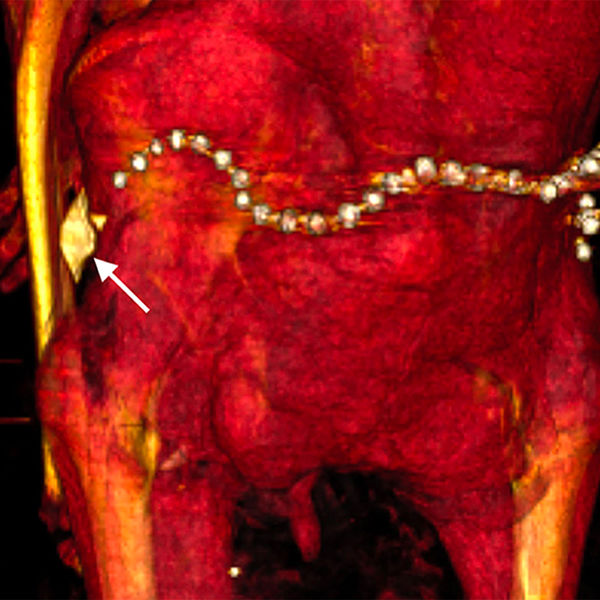

В бинтах исследователи также обнаружили около 30 украшений, в частности пояс из металлических (вероятно, золотых) бусин в задней части тазовой области, и фаянсовый амулет в форме раковины улитки у левого бедра.

Некоторые из украшений, вероятно, появились при повторном захоронении, считает Салим — так бальзамировщики хотели компенсировать ущерб, нанесенный грабителями.